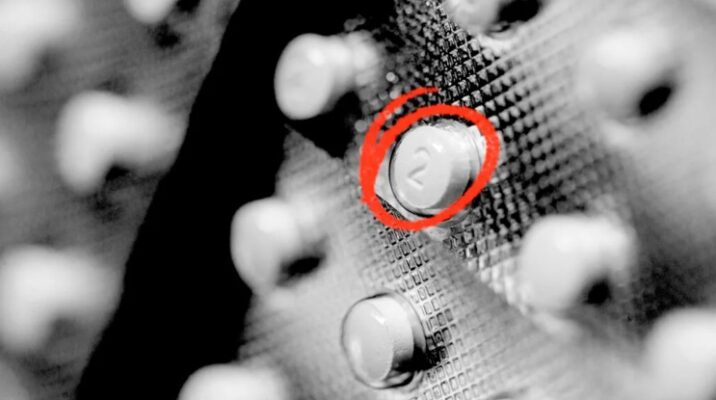

Clenbuterol is a sympathomimetic amine used by sufferers of breathing disorders as a decongestant and bronchodilator. People with chronic breathing disorders such as asthma use this as a bronchodilator to make breathing easier. It is most commonly available as the hydrochloride salt, clenbuterol hydrochloride. Clenbuterol 40mcg for sale Online in Europe.

Clenbuterol is a sympathomimetic amine used by sufferers of breathing disorders as a decongestant and bronchodilator. People with chronic breathing disorders such as asthma use this as a bronchodilator to make breathing easier. It is most commonly available as the hydrochloride salt, clenbuterol hydrochloride. Clenbuterol 40mcg for sale Online in Europe.

Clenbuterol 40mcg, or “clean,” stimulates the heart and central nervous system (CNS). It has the opposite effect as a beta-blocker and a similar effect on the body as epinephrine and amphetamines. How to order Clenbuterol 40mcg online

When people use clenbuterol legally for asthma, the dose is 20 to 40 micrograms dailyTrusted Source.

Clenbuterol 40mcg is available under various brand and generic names worldwide, including Spiropent and Monores as branded formulations, and Astralean, Ventipulmin, and other generic-labeled variants depending on region and manufacturer. While branded formulations are typically standardized in quality, generics may vary in terms of excipients, bioavailability, and tolerability — especially when sourced from disparate regions. Most generic versions contain the same active compound (Clenbuterol hydrochloride), yet formulation differences can influence absorption, onset, and side effect profile.